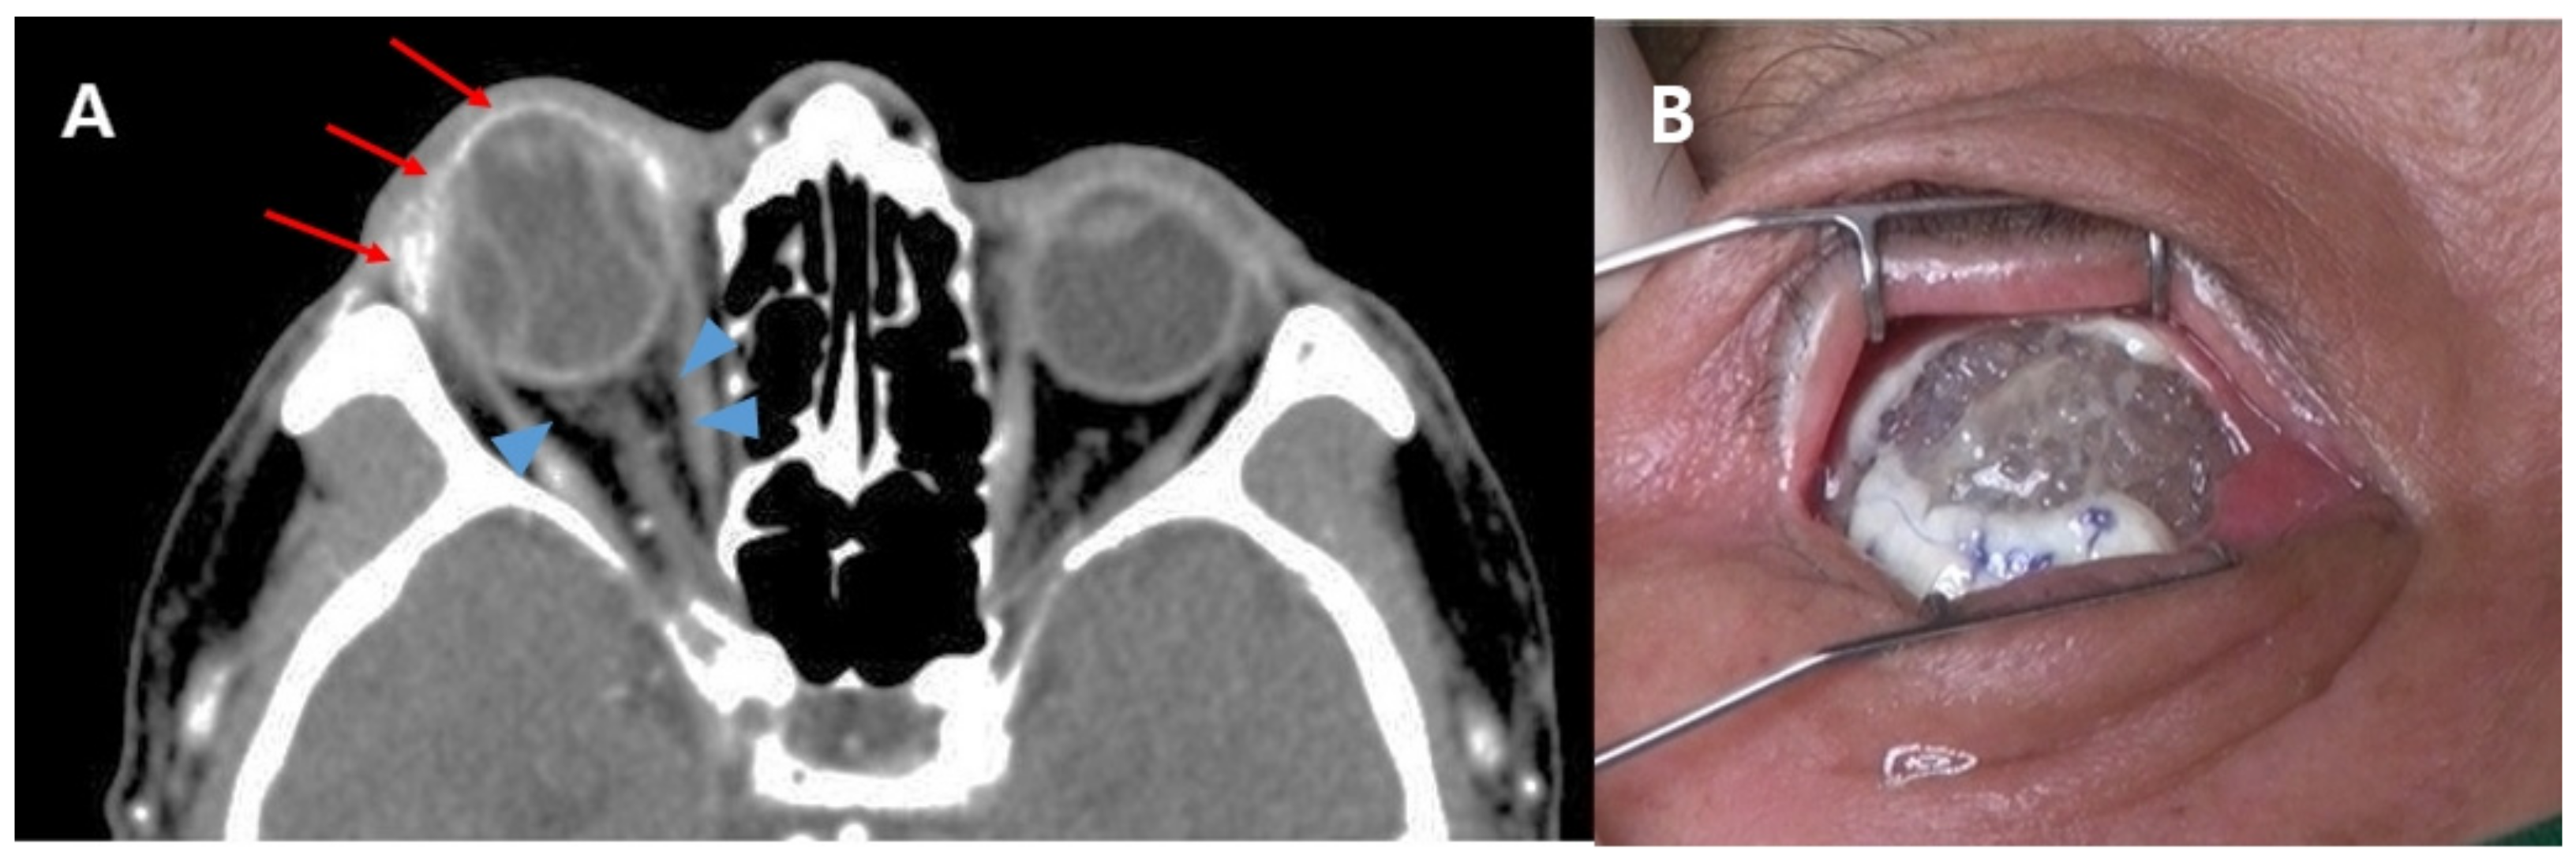

| Preoperative CT finding (n, %) | ||||

| No cellulitis | 116 (85.9) | 0 (0.0) | 0.0 | 0.999 † |

| Preseptal cellulitis | 15 (11.1) | 0 (0.0) | 0.0 | 0.999 † |

| Orbital cellulitis | 4 (3.0) | 5 (100.0) | 55.6 | <0.001 † |

| Orbital cellulitis | 320.54 (29.67 to 44,801.64) | <0.001 | 52.98 (2.18 to 15,367.34) | 0.009 |